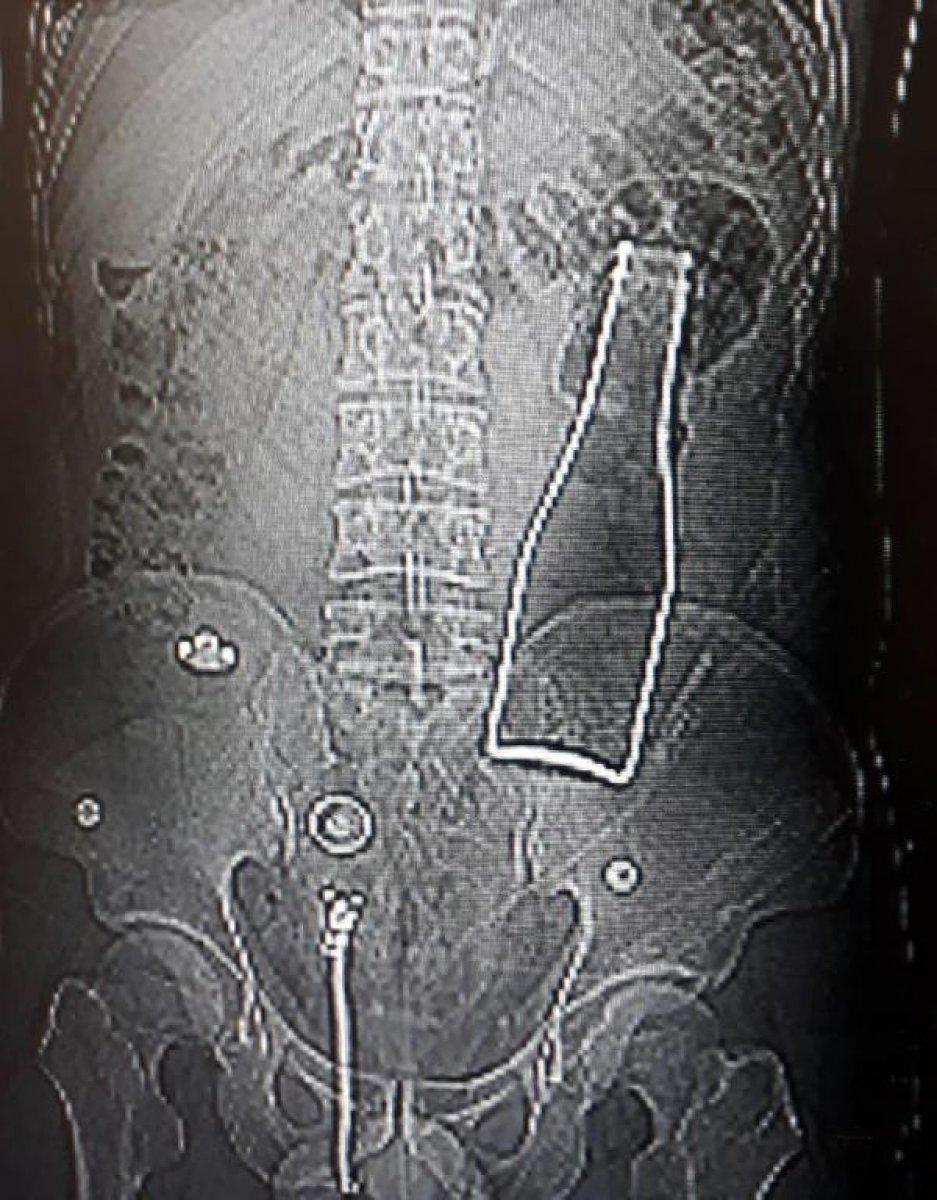

Karaman'da karın ağrısı şikayetiyle hastaneye giden Afganistan uyruklu A.E. adlı erkeğin çekilen röntgen filminde, kalın bağırsağında şişe olduğu ortaya çıktı.

Çekilen röntgen filminde, A.E.'nin kalın bağırsağının bulunduğu bölgede şişe olduğu tespit edildi.